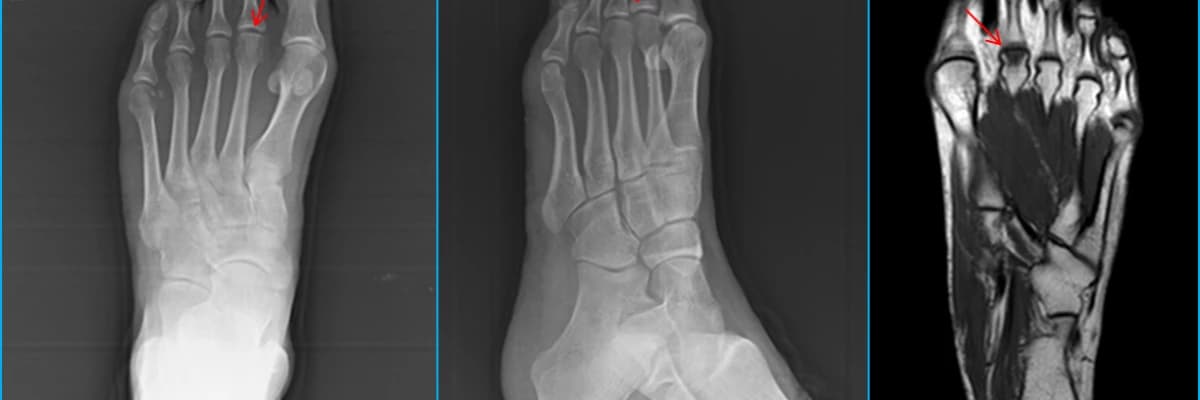

Ayak hastalıkları ile ilgili rutin incelememiz kuralına uygun şekilde çekilen röntgenografi incelemeleri ile başlamalıdır. Friberg hastalığının erken evresi (Smillie Sınıflaması Evre 1) haricinde diğer tüm evrelerde röntgenografik bulgular ortaya çıkmaktadır.Bunlar metatars başı kıkırdak altı kireçlenmeler,metatars başının düzleşmesi ve de eklem yüzünün zarar görmesidir.Evre 1 dediğimiz hastalığın en erken döneminde röntgenografi bulguları ortaya çıkmayacağı (FİGURE 1) için hastanın şikayet ve fizik muayene bulguları ışığında ayak MR inceleme ile hastalığın tanısı koyulabilir.MR da metatars başında daha çok eklem dorsal yüzüne doğru olan metatars başı ödemi (FİGURE 2) tanı koydurucudur.